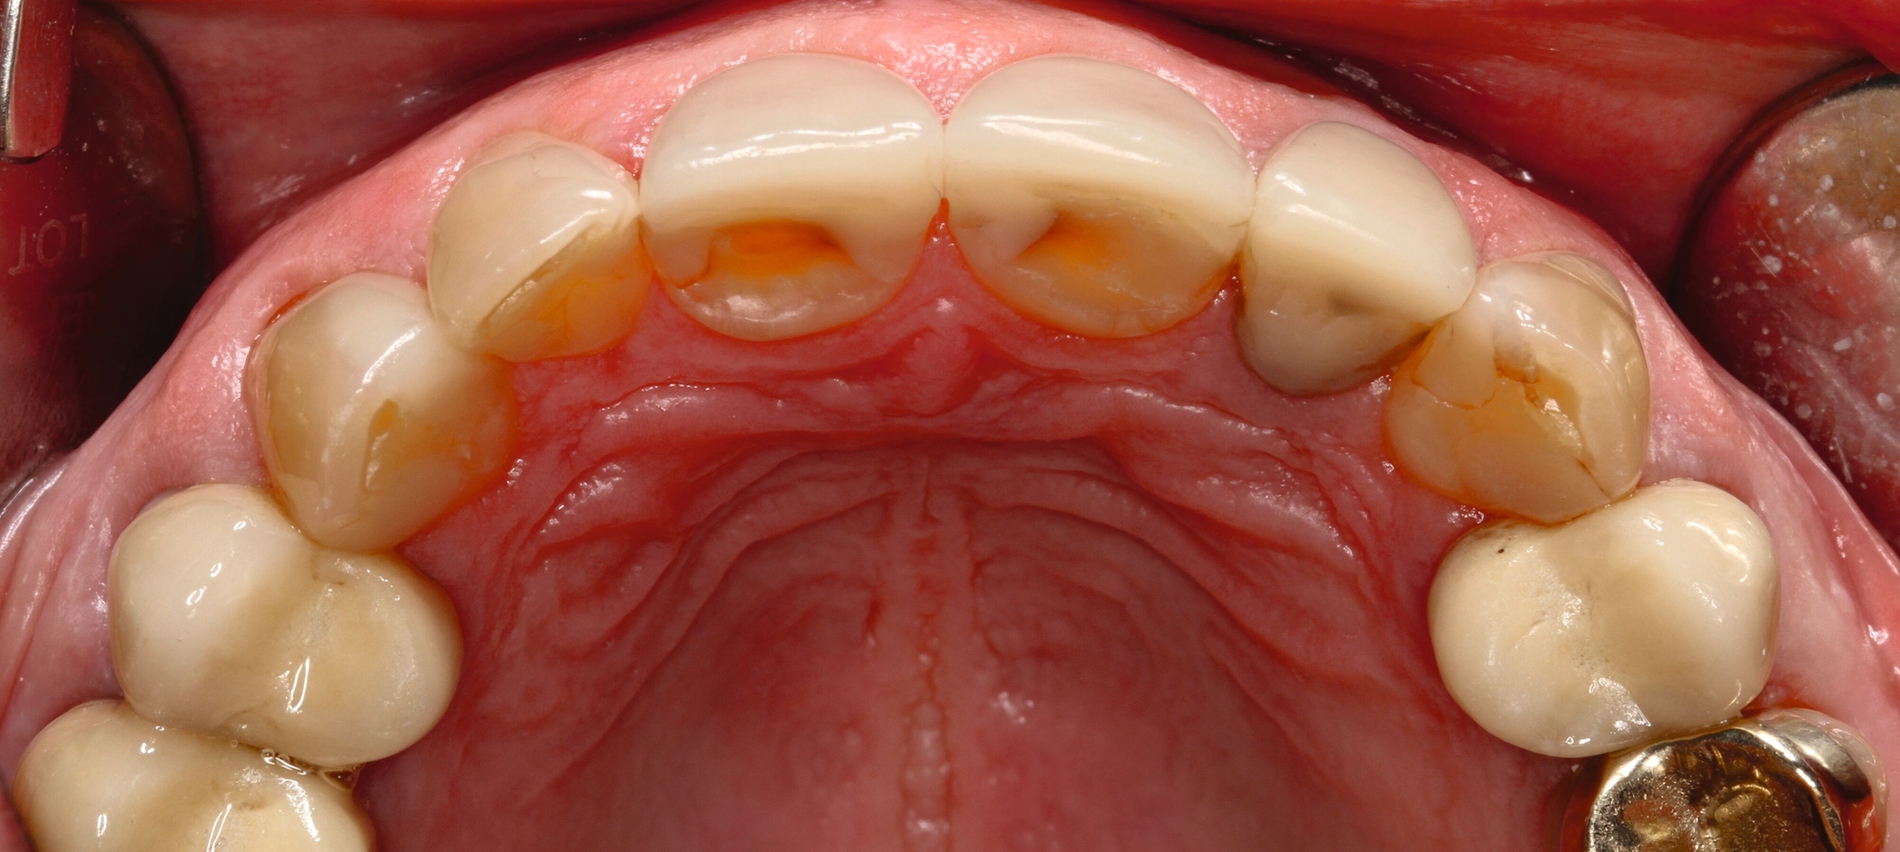

Die dentale Ausgangssituation zeigte im Seitenzahnbereich ein suffizient konservierend und prothetisch versorgtes Gebiss der zweiten Dentition sowie im Frontzahnbereich nicht kariogene Zahnhartsubstanzverluste und eine defekte Krone mit Sekundärkaries (Abbildungen 1 und 2).

Zur Verbesserung der Ästhetik und des Wohlbefindens des Patienten standen die Harmonisierung der Lachlinie und des Frontzahnbogens sowie Farb- und Formkorrekturen der Oberkieferfrontzähne im Fokus. An den Zähnen 11 und 21 waren Zahnhartsubstanzverluste durch Erosion und Attrition zu erkennen. Zahn 23 hatte ebenfalls einen erosiven Defekt, Zahn 13 eine farblich abweichende Kompositrestauration und die Zähne 14 und 24 wiesen keilförmige Defekte zervikal der Kronenränder auf, die einen suffizienten Randschluss haben (Abbildung 1a).

Die Zähne 11, 21 und 32–42 wiesen aufgrund des Zahnverschleißes stark verkürzte klinische Kronen auf. Durch diese Zahnhartsubstanzverluste sind die genannten Zähne über die Zeit elongiert – gut erkennbar an dem in Richtung Okklusionsebene verschobenen Verlauf des Gingivalsaums –, wodurch sich ein frontaler Tiefbiss und in Protrusion eine verzahnte Frontzahnführung im Schlüssel-Schloss-Prinzip mit veränderter Rot-Weiß-Ästhetik adaptiert haben. Daraus resultiert ein verringertes Platzangebot in statischer und in dynamischer Okklusion (Abbildungen 1b und 1d).